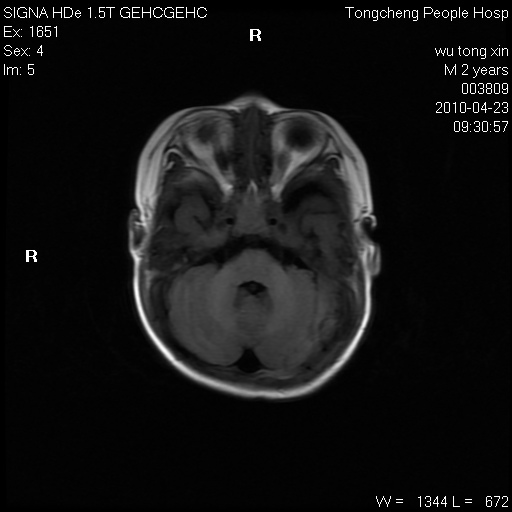

以下是引用赵物学在2010-4-25 12:43:00的发言:[br]巨脑回[br]侧脑室后角低密度影考虑hie或肾上腺脑白质营养不良?[br][br][本贴已被 赵物学 于 2010-4-25 12:51:28 修改过]

以下是引用gaoxiao在2010-4-25 16:54:00的发言:[br]巨脑回畸形。脑白质髓鞘化不良

以下是引用pujunzhi在2010-4-25 21:35:00的发言:[br]考虑 1双侧大脑皮质发育不良 2轻度脑积水 3双侧脑室后角旁片状长t1长t2信号,需继续观察,因为正常小儿此处脑白质的髓鞘化时间可以延迟到4-6岁,才显示正常。